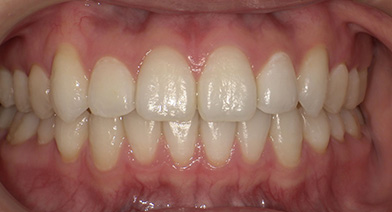

- 治療前治療後

-

下顎前突、反対咬合、上顎前歯部叢生症例

- 主訴

- 反対咬合。口元の改善

- 診療名

- 下顎前突、前歯部叢生

- 年齢・性別

- 30代女性

- 治療期間

- 4年9ヵ月

- 治療費用

- 精密検査代:39,000円

装置代:780,000円

処置代:333,000円

保定装置代:40,000円

⇒総額:1,192,000円(税込み)

※治療当時の金額となります。

- 治療説明

- 16、36、46抜歯によるスペースメイキング。

※8番があるため、6番抜歯

抜歯:上顎左側6番、下顎両側6(計3本)

治療装置:マルチブラケット装置、インビザライン

固定装置:なし

リテーナー:クリアリテーナータイプ

- リスク・副作用

- 痛み・治療後の後戻り・歯根吸収・歯髄壊死・歯肉退縮

症例の詳細を見る